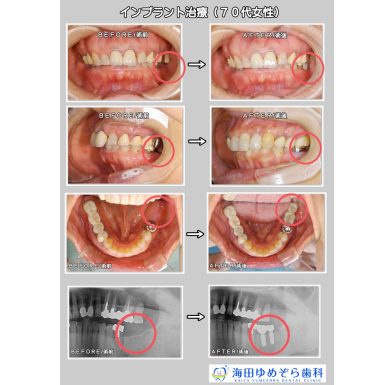

インプラントの症例

☆治療内容

インプラント

☆治療期間

5ヶ月

☆治療費用

¥440,000×2本 トータル¥880,000(税込)

☆リスク

術後の出血、腫れ、痛みの可能性があります